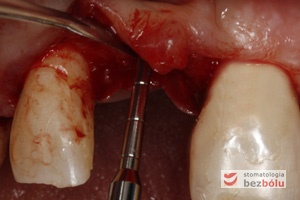

Mapowanie kości - diagnostyka grubości błony śluzowej przy użyciu instrumentu endodontycznego

Mapowanie kości – diagnostyka grubości błony śluzowej przy użyciu instrumentu endodontycznego